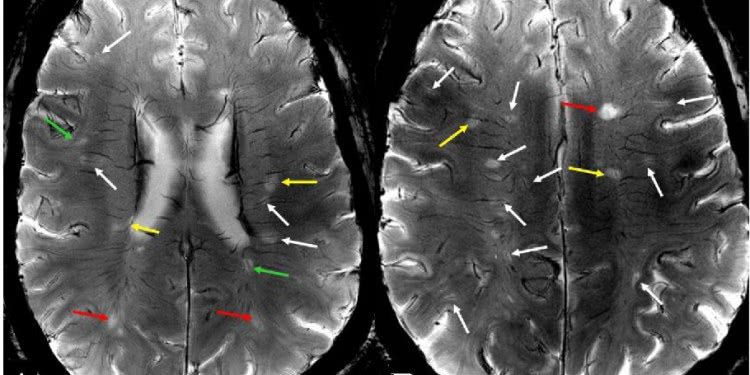

Цель — описать перивенозную взаимосвязь поражений РС на изображениях, чувствительных к чувствительности 7Т МР высокого разрешения и контрастности. Результат — Мы демонстрируем заметно улучшенное обнаружение уникального микрососудистого поражения, которое связано с большинством визуализированных поражений РС с аномальными сигналами на и вокруг венозной стенки на 7Т по сравнению с 3Т МРТ.

Выводы — эти выводы которые никогда не были показаны на обычной области МРТ, не только позволяют получить прямые доказательства патогенеза сосудов при рассеянном склерозе in vivo, но и имеют важное значение для мониторинга активности поражения и терапевтического ответа на лечение. Вскоре после первого изображения в начале 19-го века, рассеянный склероз (РС) получил признание как прогрессирующее и инвалидизирующее нейродегенеративное заболевание. Хотя сосудистый патогенез связанный с аутоиммунным разрушением миелина аутореактивными Т-лимфоцитами, давно предполагался, степень микрососудистых аномалий и их точную связь с развитием поражения было трудно оценить и оценить in vivo до недавних значительных достижений в МР. Методы МРТ со сверхсильным полем (> 3T) благодаря увеличенному отношению сигнал / шум (SNR) и усиленным эффектам восприимчивости, обеспечивающим заметно улучшенное разрешение и контрастность изображения, имеют большой потенциал для оценки венозной сосудистой сети на ранних стадиях развития поражения. Мы описываем 7Т МРТ у двух пациентов с ремиттирующим РС и связываем наши наблюдения с ранними микрососудистыми аномалиями как первичное свидетельство развития повреждений in vivo.